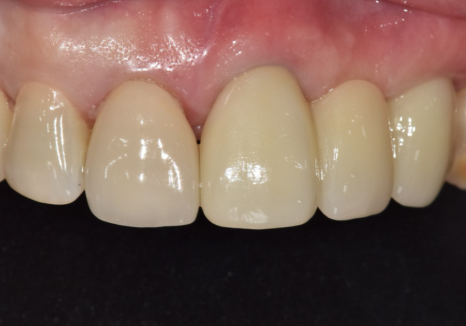

오래된 앞니 크라운 냄새, '이것' 때문일 수 있습니다.

앞니 임플란트는

단순히 튼튼하게 심는 것을 넘어

'옆 치아와 얼마나 자연스럽게 어울리는가'가

생명입니다.

특히 이 환자분처럼 주변 치아도 크라운인 경우,

색상이나 각도가 조금만 어긋나도

매우 어색한 인상을 줄 수 있는데요~

저희가 최적의 결과를 낼 수 있는 비결은

치과 내부에 전용 기공소가 있기 때문입니다.

어떠세요? 주변 치아와 조화를 이루며

아주 자연스럽게 마무리된 모습이죠?

단순히 심는 것에 그치지 않고

뼈 상태, 잇몸 회복,그리고 정교한 교합까지

세밀하게 고려하여 자연스러운 보철이

완성되었습니다.^^